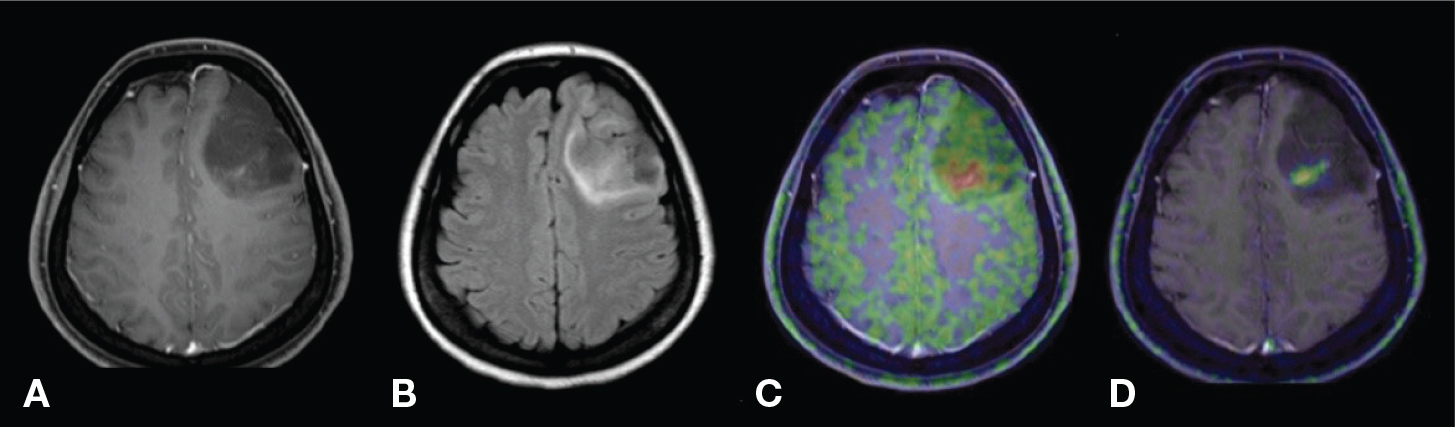

Glucose uses both the facilitated diffusion glucose transporter (GLUT) family and the sodium-glucose linked transporter (SGLT) family to enter brain cells. Due to increased glycolysis and the TCA cycle, these transporters are upregulated in brain tumor cells, resulting in high concentrations of glucose inside the cell that facilitate energy production (10, 43). 18F-FDG and 18F-Me-4DFG are two glucose analogues that use the increased number of glucose transporters to image brain tumor cells. 18F-FDG mainly uses GLUT-1 and to a lesser extent GLUT-3, both which are present on the BBB (Table 2); after entering the cell, it is phosphorylated and becomes trapped as 18FDG-6-phosphate (Figure 2). 18F-Me-4FDG uses SGLT2, which is not present on the healthy BBB, rather only on endothelial cells of tumor vasculature (Table 3); after entering the cell it becomes trapped without phosphorylation (Figure 2). In clinical practice, uptake of either agent will reflect overexpression of the transporters and therefore (indirectly) increased energy metabolism. The BBB does not hamper the uptake of 18F-FDG, and the uptake of 18F-Me-4FDG will additionally reflect increased tumor vasculature +/− BBB leakage. Since energy metabolism generally increases with increasing malignancy grade, 18F-FDG has often been used to differentiate between WHO grades, and recently even between IDH-mutated and IDH-wildtype tumors (44). It can also help differentiate tumor recurrence from treatment-related changes, and recent radiomics techniques with also show promise in predicting Ki-67 expression and patient prognosis non-invasively (45, 46). The main limitation of 18F-FDG lies in the generically high rate of glucose metabolism in the healthy cerebral cortex, leading to low tumor-to-normal-tissue (T/N) ratios for most tumors except those with very high cellular density and metabolic rate, like lymphoma (47). 18F-Me-4FDG does not have this problem since it does not cross the healthy BBB, causing a very low uptake in healthy brain tissue and consequently high T/N ratio, which is its main advantage over 18F-FDG (Figure 3) (48). For both agents, a major limitation is their intrinsic low tumor specificity: increased glucose consumption is also seen in other non-oncological processes such as (acute) inflammatory tissue, although 18F-Me-4FDG might prove more tumor-specific due to its inability to cross the BBB (49).

Figure 3. 18F-Me-4FDG PET (left), T1-weighted post-contrast (middle) and 18F-FDG PET (right) images of a patient with an anaplastic astrocytoma, WHO grade III. The 18F-FDG image shows mixed uptake within some portions of the mass, with highest uptake comparable to normal cortical uptake in the healthy contralateral cortex. The 18F-Me-4FDG image, however, shows uniform tumor uptake without any uptake in the surrounding healthy brain parenchyma, providing significantly higher T/N ratio than the 18F-FDG image. This figure is reproduced – with new figure legend appropriate for current book chapter – from Kepe et al. (2018), Figure 4, under the terms of the Creative Commons Attribution 4.0 International License (http://creativecommons.org/licenses/by/4.0) (48).